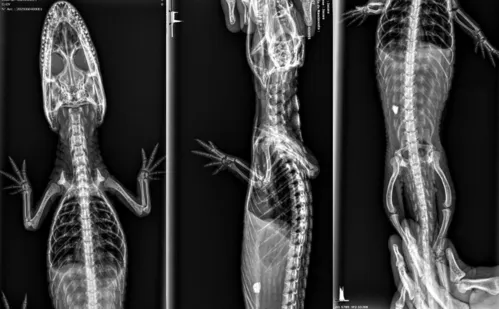

Curupira: jacaré resgatado em Vila Velha ganha nome e passa por exames

Animal passou por exames de raio-X. Veja imagens

Apesar da leve melhora inicial, jacaré ainda não tem forças para se alimentar sozinho e está recebendo alimentação por sonda |  Foto: Divulgação/Projeto Caiman

De acordo com o Projeto Caiman, que realizou o resgate, o jacaré foi batizado de Curupira, em homenagem ao Dia do Meio Ambiente. Ele, que chegou debilitado, magro, desidratado e sem forças nem para manter a cabeça erguida, passou por exames e segue recebendo alimentação por sonda.

Animal passou por exames de raio-X |  Foto: Divulgação/Projeto Caiman

Segundo o médico veterinário Gabriel Breder, foram realizados exames de raio-X e coleta de sangue, além da aplicação de fluidoterapia intra óssea — um procedimento emergencial que acelera a reidratação. Nas imagens, uma possível obstrução no sistema digestivo foi identificada.

"A equipe médica está acompanhando o caso para verificar se o jacaré conseguirá eliminar o bloqueio naturalmente ou se será necessária uma cirurgia", informou o Projeto Caiman, por meio de assessoria. A equipe disponibilizou, também, imagens atualizadas do animal, feitas no hospital veterinário: